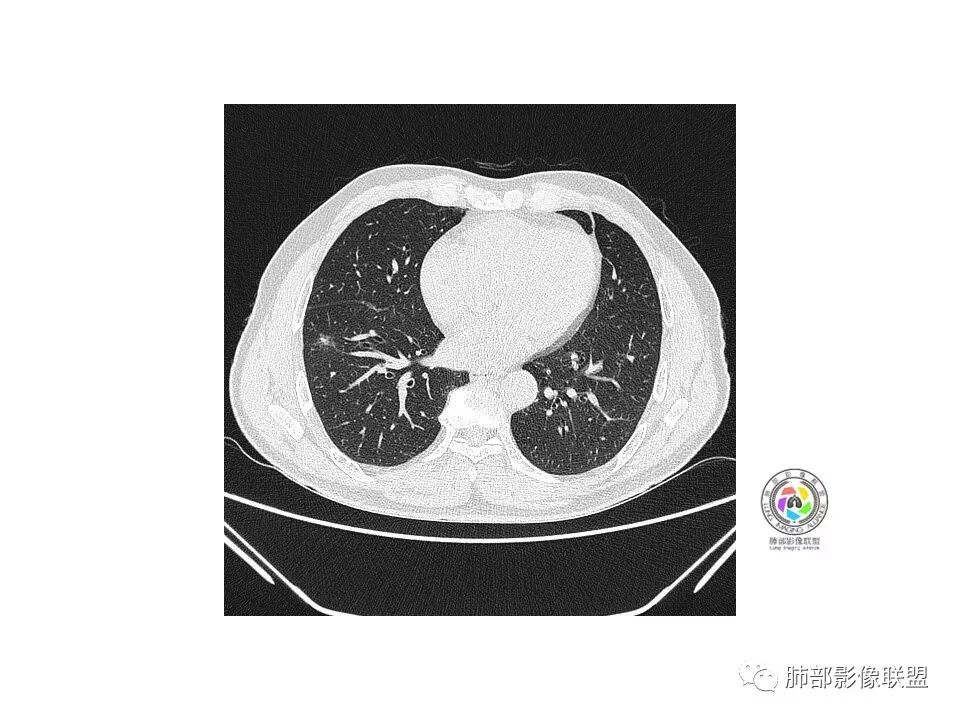

病史:老年男性,咳、痰三天;

1.纵膈窗未显示;水平裂有轻微凹陷,那个条索影,有形成机理进一步分析;前方那个血管,可能是肺动脉?有一定弯曲度(向病灶),后方这个是肺静脉;3个小叶凹,有可能,受到阻挡,邻近小血管有相应改变;薄层那个细小血管有弯曲,形成部分实性;

2.大小:估计15*10mm左右;

3.CT值:混杂,有些偏高;

4.周围小血管,有形成毛刺趋势;

5.血管:如上述;

6.胸膜和叶间裂:有轻微牵拉;

诊断:浸润性腺癌;鉴别:炎性结节;

处理:炎标、肿标、病史、职业史、抽烟史,既往胸部检查;

老年男性,咳嗽、咳痰3天。胸部CT:右肺下叶前基底段mGGN,边缘清楚,内可见不规则实性成分,病灶可见空泡、毛刺、胸膜牵拉、血管集束征象。考虑MIA可能大,抗炎2W后复查。

老年男性,右下肺前基底段混合GGN,边缘清晰,月牙铲,叶间胸膜牵拉,有轻度收缩力。结合病史抗炎2-3周后复查,消失考虑炎症,变化不大为腺癌。本例总体支持腺癌

老年男性,咳嗽3天,右肺下叶前基底段混合磨玻璃结节,形态不规整,相邻胸膜凹陷,可见血管影,考虑腺癌可能性大,不除外炎症可能,建议抗炎1~2周,1个月复查胸部CT。

右肺下叶mGGN,内部结构紊乱,可见小点状高密度影,边缘清晰,小叶间隔阻挡,轻度收缩力,考虑MIA,常规飞一会20天复查。